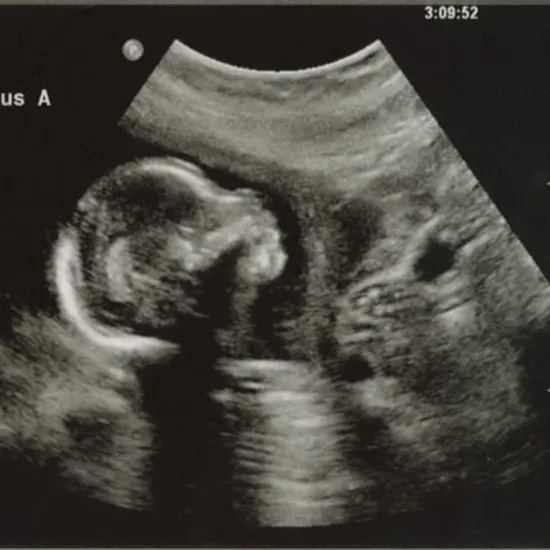

USG testing involves scanning the body's internal organs with high-frequency sound waves to determine their condition. During a USG level II examination, an ultrasound scan of the area below the abdomen (pelvis) is performed, allowing a detailed view of the baby's development in the mother's womb. The scan reveals the baby's heart, stomach, brain, and kidneys.

It helps with the management of multiple/twin pregnancies and the complications that may arise. During the second trimester of pregnancy, this scan is performed (18 to 22 weeks).